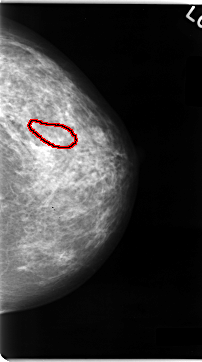

C_0060_1.RIGHT_MLO

FILE: C_0060_1.RIGHT_MLO.OVERLAY

TOTAL_ABNORMALITIES 1

ABNORMALITY 1

LESION_TYPE MASS SHAPE ROUND MARGINS CIRCUMSCRIBED

ASSESSMENT 3

SUBTLETY 5

PATHOLOGY BENIGN

TOTAL_OUTLINES 1

BOUNDARY